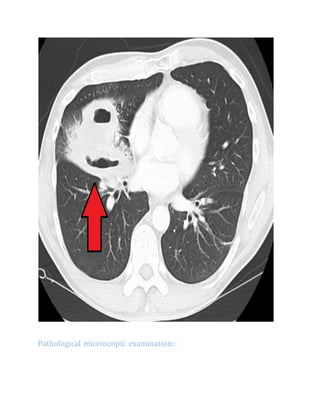

CT scan:-

the thorax right upper lobe shows a thick-walled cavity.

Pathological microscopic examination:-

Pathology image of a lung abscess.